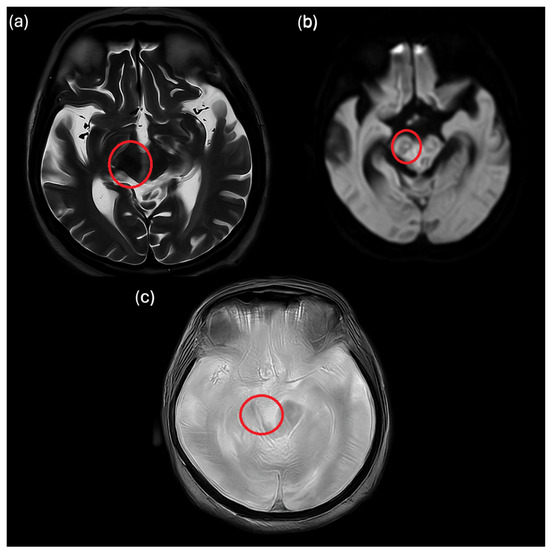

Background: Neurocysticercosis is a parasitic infection of the central nervous system caused by the larval stage of Taenia solium. This disease is endemic in some countries in Central and South America, South and South-East Asia, and sub-Saharan Africa. In North America, [...] Read more.

Background: Neurocysticercosis is a parasitic infection of the central nervous system caused by the larval stage of Taenia solium. This disease is endemic in some countries in Central and South America, South and South-East Asia, and sub-Saharan Africa. In North America, Europe, Japan, and Australia, only sporadic cases are documented. Moreover, reports of bacterial superinfection arising within neurocysticercotic lesions remain exceptionally scarce. Methods: We report a clinically severe and diagnostically challenging case of suspected neurocysticercosis with cerebral streptococcal superinfection in a 17-year-old Italian patient with Down syndrome and no history of travel to endemic regions. Results: The patient, with pre-existing epileptic encephalopathy, presented with progressive drowsiness and altered mental status, rapidly deteriorating to cardiorespiratory arrest. Neuroimaging demonstrated multiple ring-enhancing lesions, in conjunction with positive Taenia solium serology. Streptococcus spp. was identified in one neurosurgically drained lesion, consistent with secondary bacterial involvement in association with concurrent pneumonia. Combined antiparasitic therapy and targeted antimicrobial treatment resulted in sustained clinical and radiological improvement. Conclusions: In non-endemic settings, neurocysticercosis should remain within the differential diagnosis of unexplained epilepsy and multifocal CNS lesions. Although rare, bacterial superinfection warrants consideration in atypical presentations, particularly in individuals with concomitant infectious foci and underlying immune dysfunction such as that associated with Down syndrome. Full article

Show Figures

Figure 1